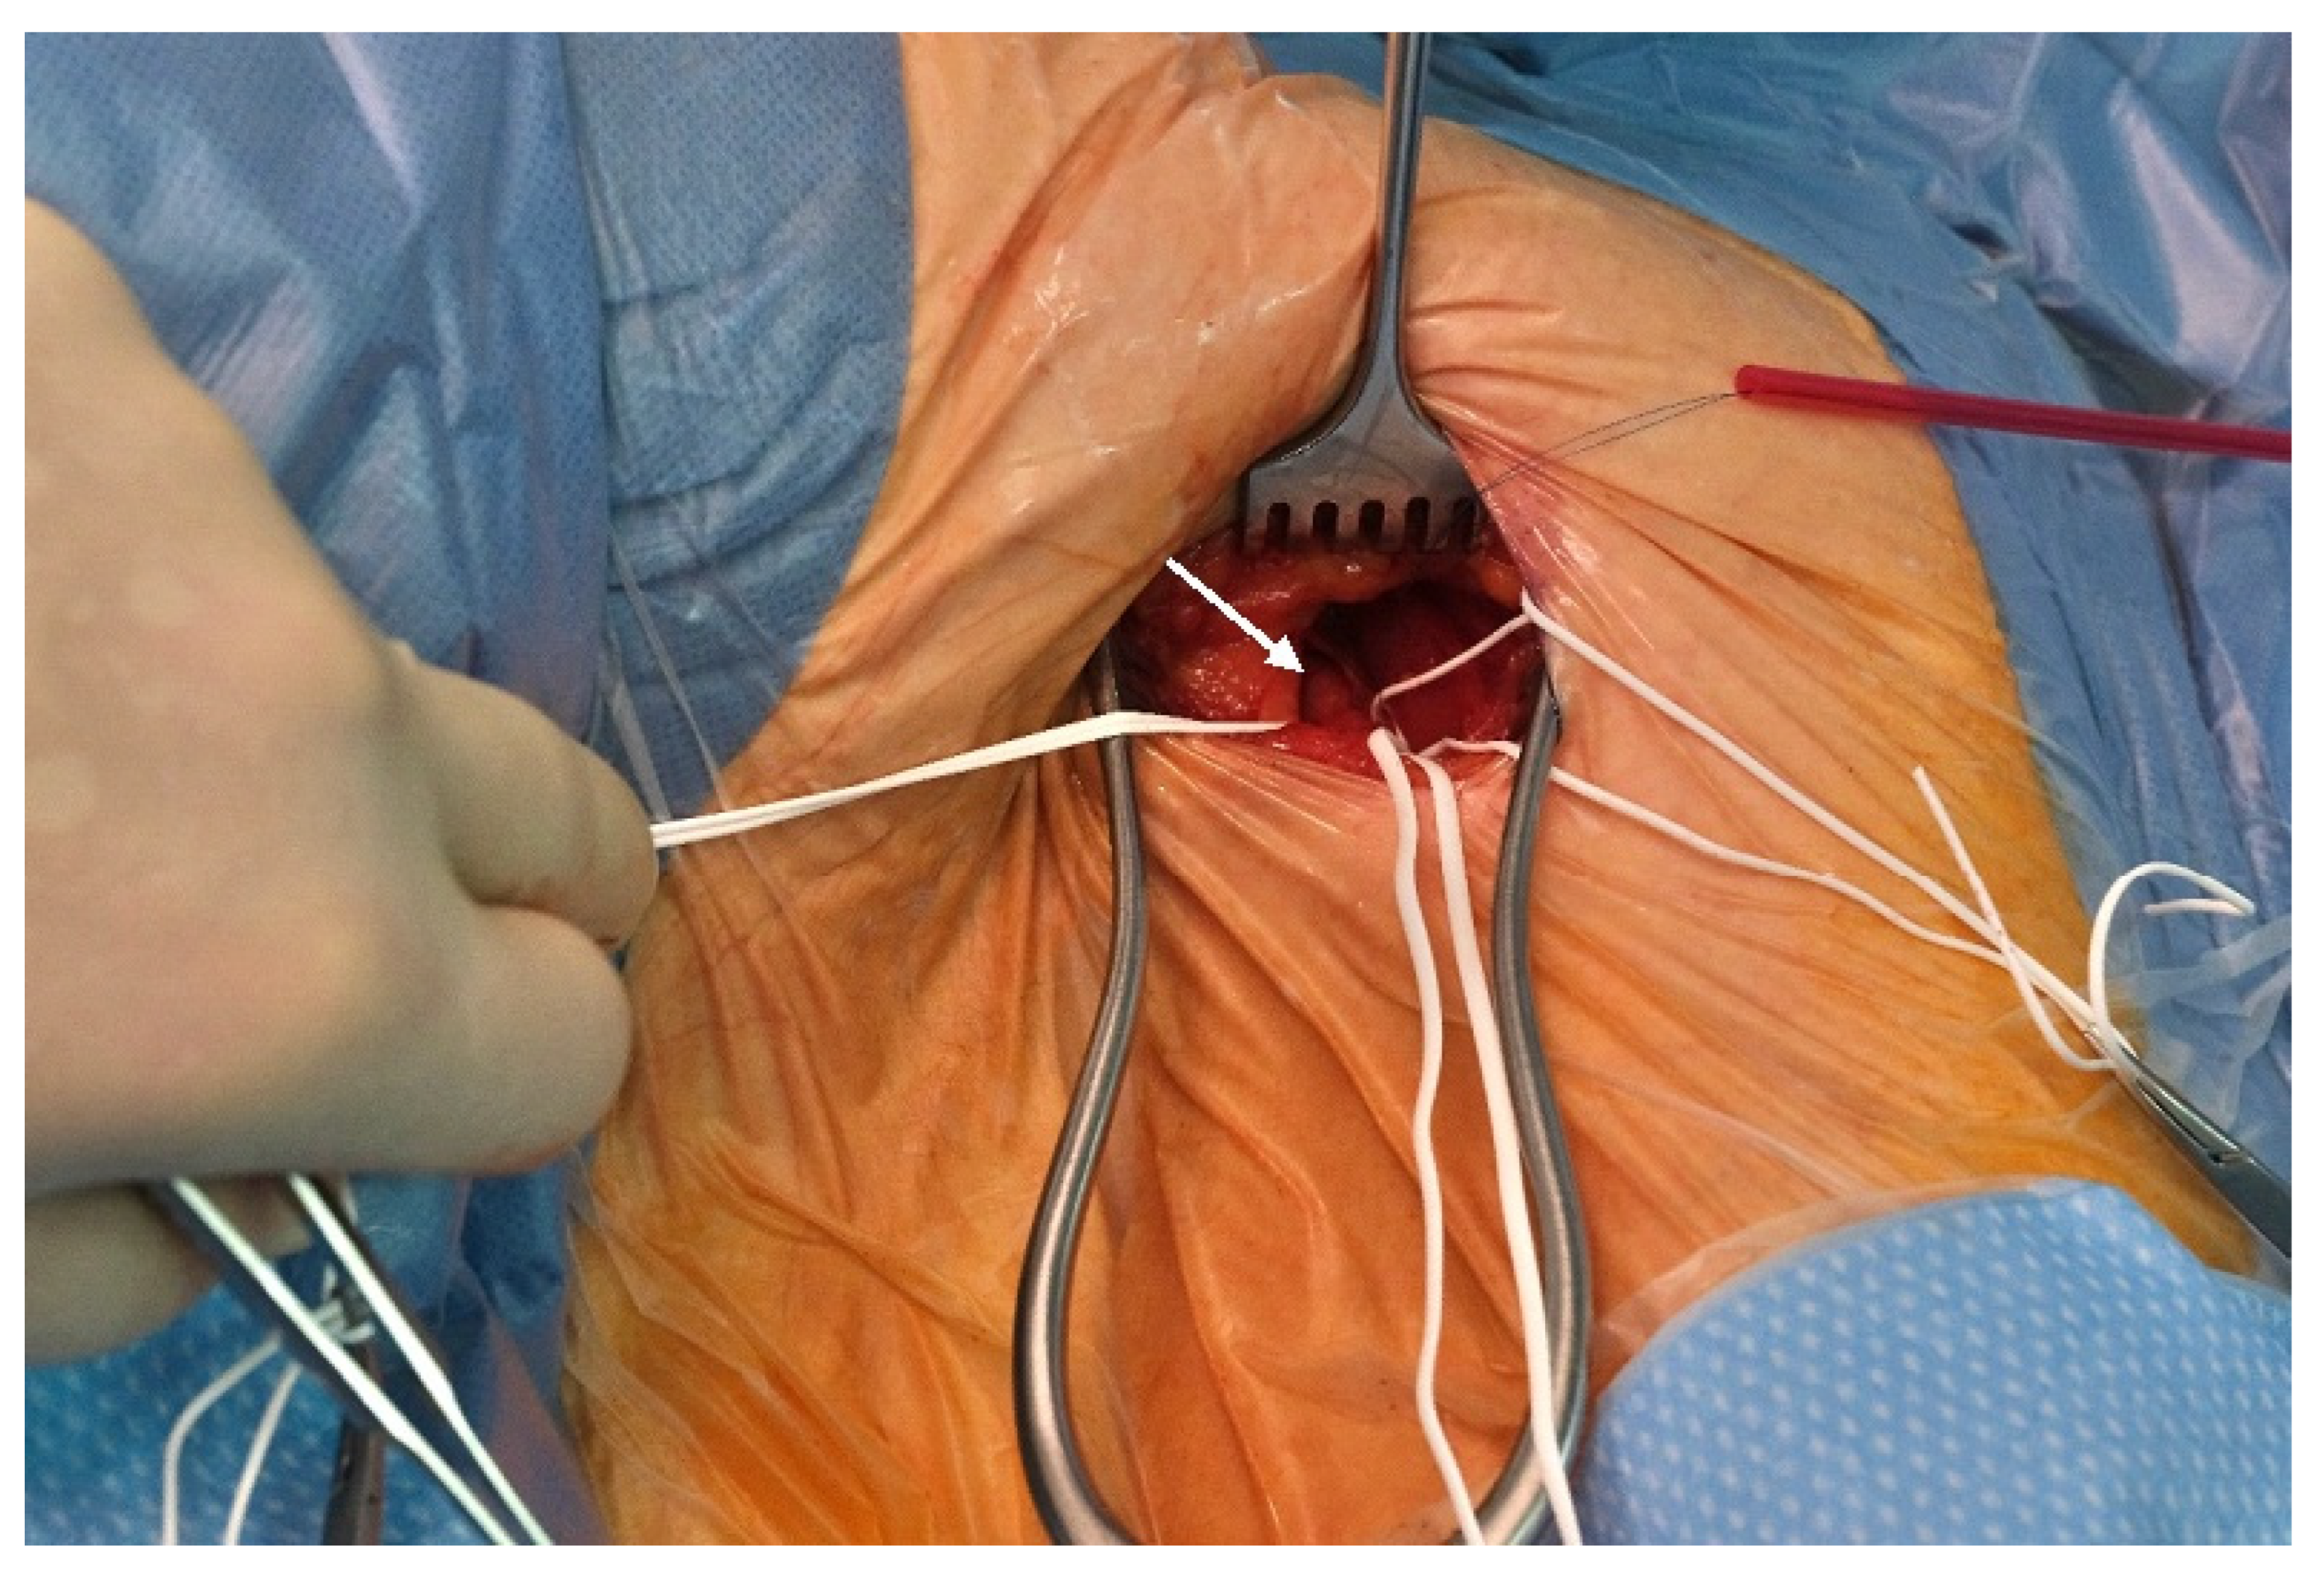

2.2. Preoperative Planning and Operative Technique

4.2. Benefits of the Surgical Approach